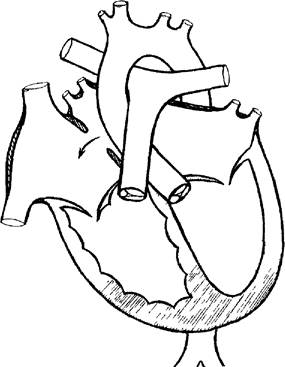

Рис. 2. Схема сердца с вторичным дефектом межпредсердной перегородки (стрелкой указано направление шунта).